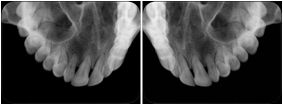

3. A dental provider wishes to capture a series of DICOM IO images for the patient’s dentition. The tooth morphology, teeth are divided into molars, premolars, canines and incisors, and a number of images for each jaw. The anatomic information was captured utilizing the triplet of schema. This standard code sequence is based on ISO 3950-2010, Dentistry - Designation system for teeth and areas of the oral cavity.

Every IO image should have anatomic information either through the primary or modifier sequence.

In most standard cases, images are oriented in structured layouts. These structured displays are useful to be shared between providers for reference purposes.

Table OO.1.1-1 shows structured display standard templates, where Viewset ID is based on the Japanese Society for Oral and Maxillofacial Radiology (JSOMR) classification provided by JIRA (Japan Medical Imaging and Radiological Systems Industries Association, www.jira-net.or.jp). Expected or typical teeth to be imaged location, region and designation codes are based on ISO 3950-2010, Dentistry - Designation system for teeth and areas of the oral cavity. For all the hanging protocols listed in OO.1.1-1, the value to use for Hanging Protocol Creator (0072,0008) is "JSOMR" and the value to use for Hanging Protocol Name (0072,0002) does not include "JSOMR" (e.g., "DL-S001A", not "JSOMR DL-S001A").